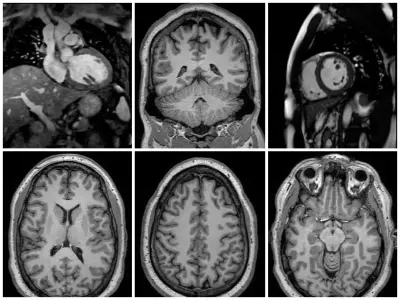

Proporciono soporte científico y técnico de Resonancia Magnética a una red de más de 15 hospitales y centros de investigación de referencia en Iberia, centrándome en estudios neurológicos y de abdomen.

Colaboro en proyectos de investigación, ayudo a optimizar protocolos de adquisición y reconstrucción, y actúo como puente entre las necesidades clínicas y las soluciones tecnológicas de Philips.

Desarrollé nuevas secuencias de RM para aplicaciones cardiovasculares y hepáticas, trabajando en St. Thomas' Hospital.

Mi trabajo se centró en secuencias de RM multiparamétricas, principalmente MR Fingerprinting.